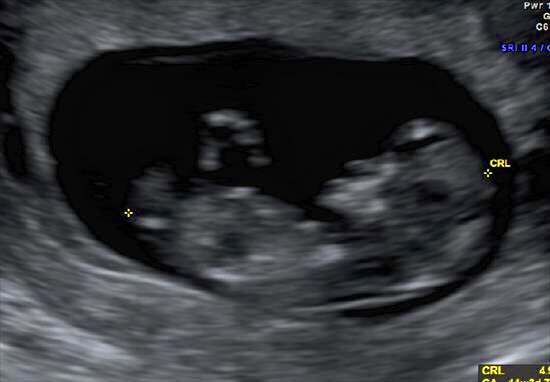

Attachment 28101 2nd pic!

Very girly

Thank you, it looks girly but it is still too early for accurate guesses, it could still rise at this point.

girly

Looks girly to me